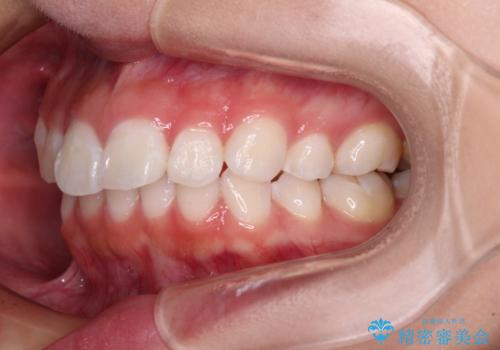

- 上下前歯の叢生を気にして来院された患者様です。

インビザラインでの治療を希望されていて、デコボコの程度が中等度であり、安価なパッケージにて対応可能と判断されたため、インビザライン・モデレートを用いて矯正治療を行うこととしました。

インビザライン・モデレートは、製作できるアライナーの枚数に制限があるため、移動可能な量に限りがあるものの、インビザライン・ライトよりも枚数が多いため、幅広い症例に対応可能です。